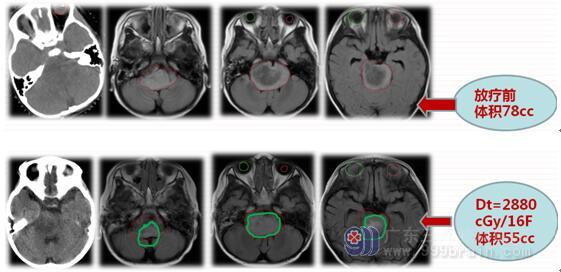

考虑II-III级胶质瘤可能,遂展开治疗。首先放疗定位,同步替莫唑胺75mg/㎡ ,20%甘露醇+激素 脱水,次日上午开始进行适形放疗,第一阶段给予剂量180cGy*22F。患儿体温下降至35.2--35.8℃,心率由入院时的90bpm下降至50-60bpm,GCS评分下降至7分。家属知情同意后,给予贝伐珠单抗10mg/kg 100mg ivd治疗,患儿生命体征趋向平稳,继续放疗。

治疗后患儿情况明显好转,2016年6月16日,患儿病灶缩小23cc。于5个月后,患儿KPS=100分,治疗8个月后随访患者仍存活。

2017-3-16治疗8月后